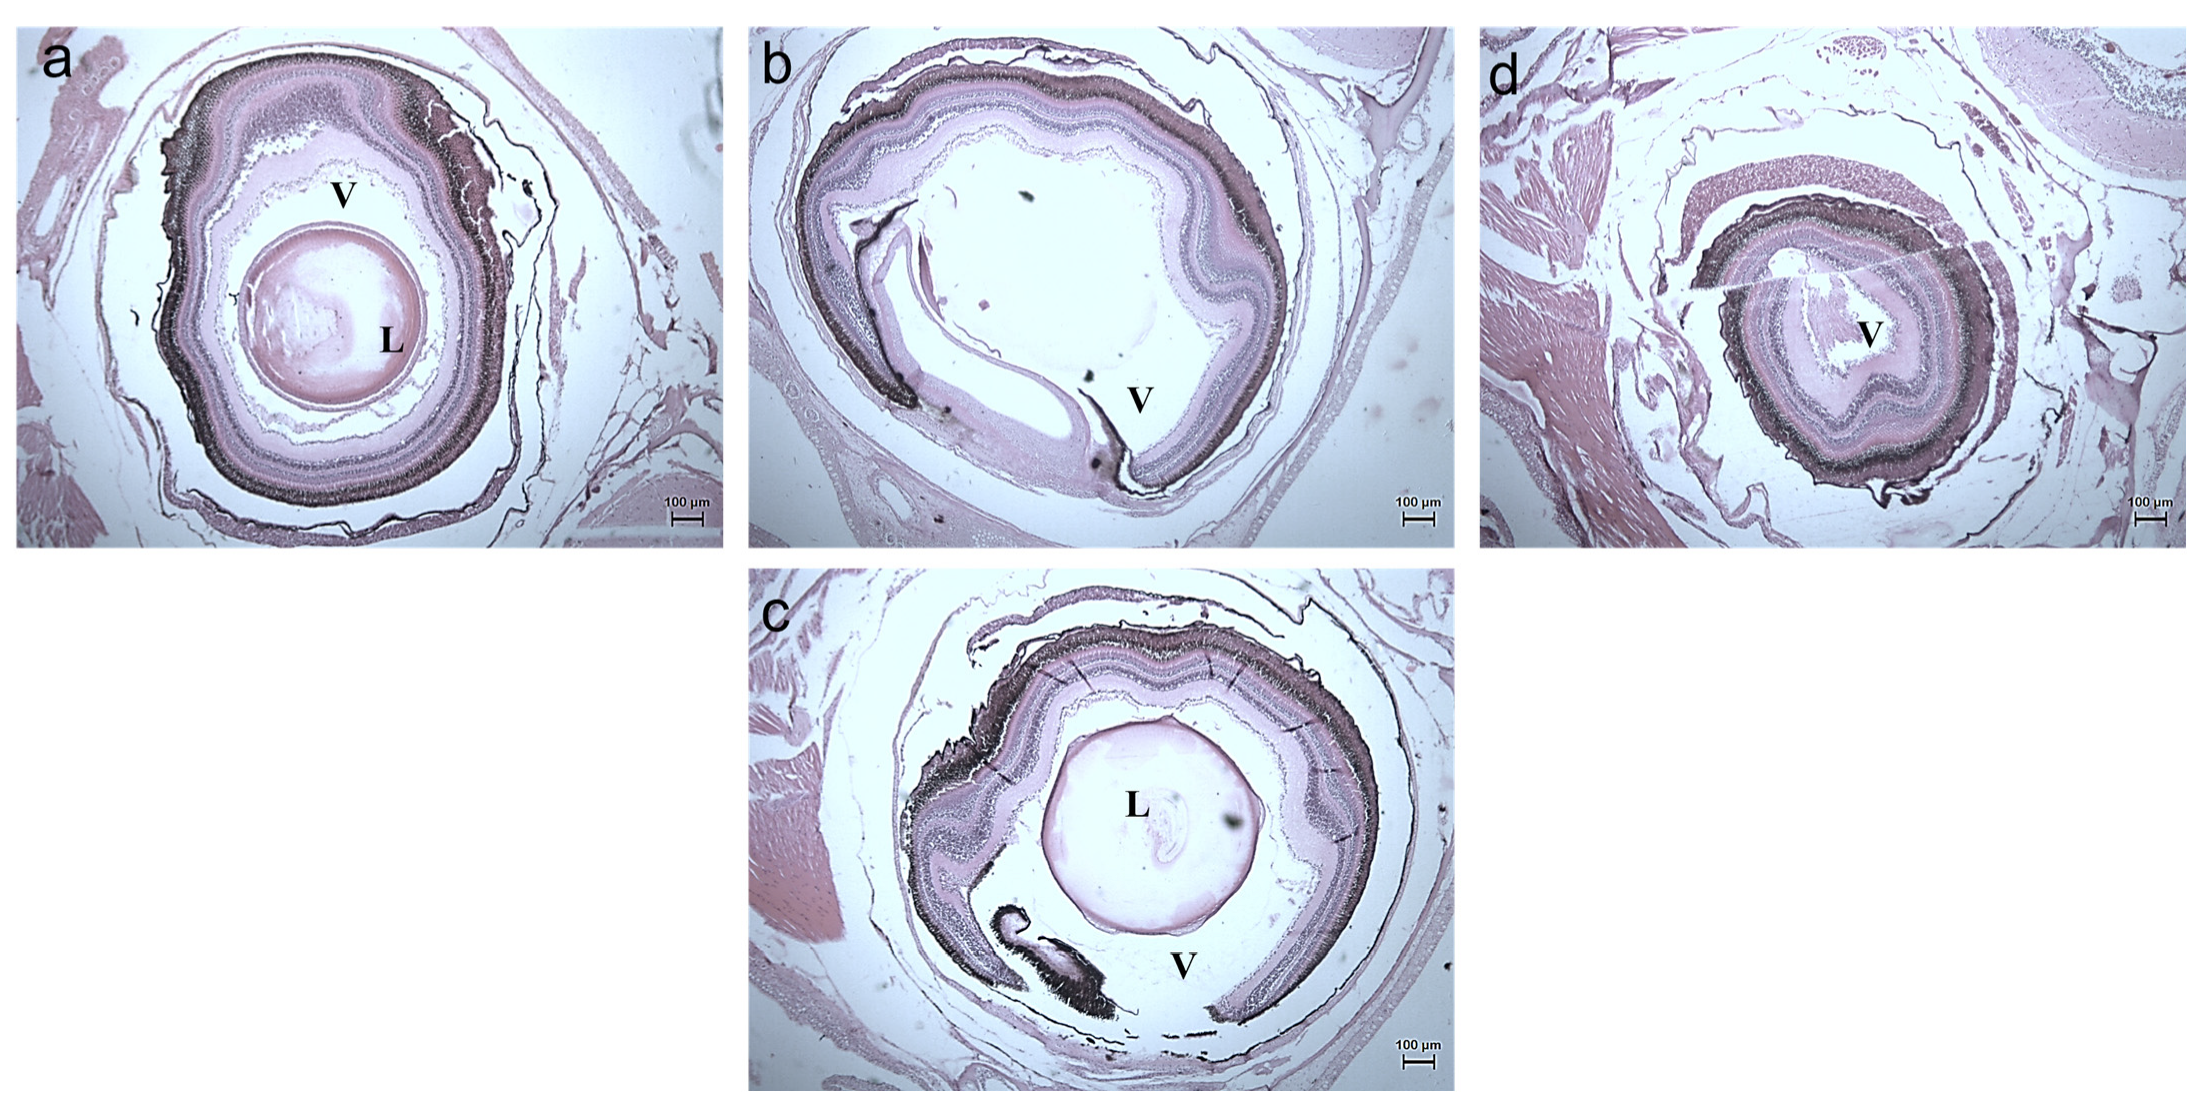

3.2.3. Histology Studies